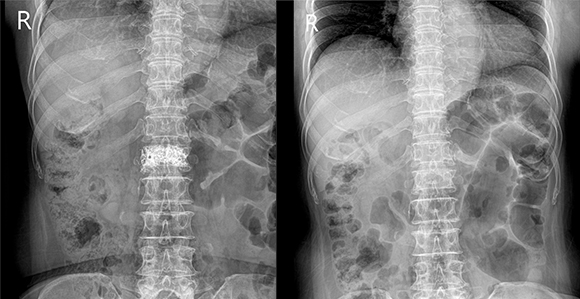

골절이 되어 어긋나 있는 뼈를 맞추는 것을 정복이라고 하며, 도수 정복은 수술 없이 골절된 뼈를 바로 맞추는 시술입니다. 골절 후 6시간 내지 12시간이 경과하면 부종이 증가하기 때문에 정복은 조기에 시행할수록 좋습니다. 임상적 판단에 의하여 합당한 경우에 숙련된 의사에 의하여 시도되어야 하며 정복의 시행 전후로 방사선 사진을 촬영하여 정복의 적절성을 확인합니다. 적절한 정복이 이루어진 후 여러 방법으로 고정하게 됩니다.

미세 골절이나 골절된 뼈가 틀어지지 않는 경우 일차적인 골 유합이 이루어질 때까지, 일반적으로 ‘반기브스’라고 불리는 석고 부목, ‘통기브스'라 불리는 석고붕대 고정, 보조기를 이용하는 방법 등이 있으며 견인에 의한 고정을 시행하기도 합니다.